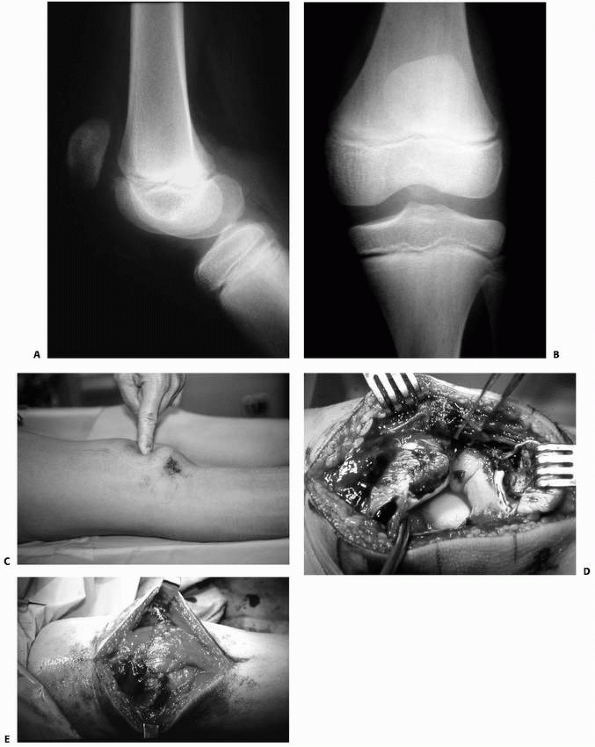

FIGURE 23-5 A.

Completely displaced Salter-Harris type II fracture of the distal femur in a 6-year-old girl whose foot was on the back of the driver’s headrest when the automobile in which she was riding was involved in an accident. B. Ecchymosis in the popliteal fossa and anterior displacement of the distal femur are evident. Clinical examination revealed absence of peroneal nerve function and a cold, pulseless foot. |

![]() |

FIGURE 23-5 (continued)

The fracture was irreducible by closed methods and required open reduction, internal fixation, and repair of a popliteal artery laceration. C,D. Incomplete reduction Salter-Harris type II fracture in a 6-year-old girl with 25 degrees of posterior angulation and abundant callus formation. E,F. Four years later, remodeling has occurred and no growth disturbance is noted. Results such as this cannot be relied upon, and early anatomic reduction is recommended. |